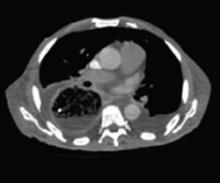

A stat CT of the patient’s abdomen and pelvis revealed no signs of obstructive uropathy to explain his acute renal failure. A sagittal CT reconstruction in bone windows of the initial ED radiological workup was revealing (FIGURE 1).

FIGURE 1

Sagittal CT reconstruction of thoracolumbar spine

The sagittal CT reconstruction in bone windows of the thoracolumbar spine (FIGURE 1) revealed multiple lucent foci throughout the osseous structures, with an anterior compression deformity of the L2 vertebral body. A subsequent skeletal survey showed a diffuse salt and pepper pattern affecting most of the osseous structures, with additional lytic lesions in the calvarium and extremities.